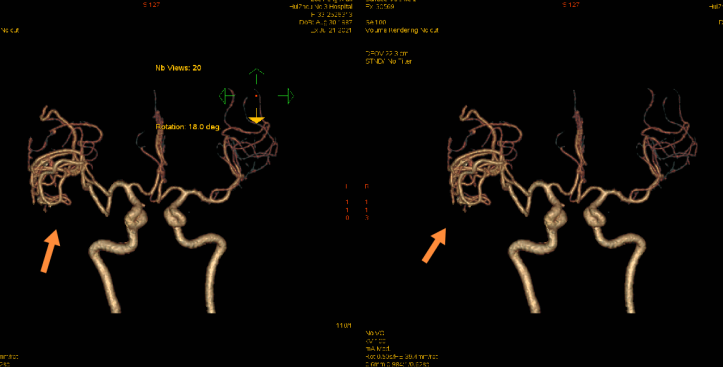

CTA影像檢查(箭頭為畸形血管團)